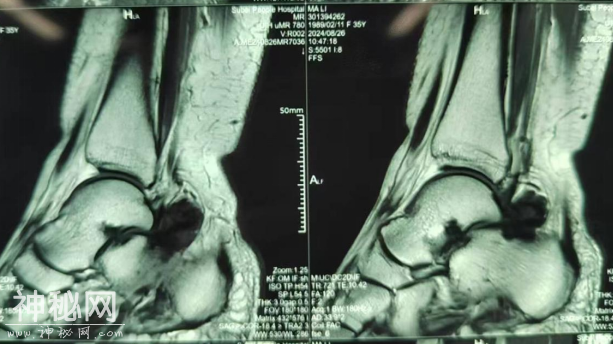

最近马女士觉得疼痛感愈发加重,来到市六医院金山分院诊治,接诊医生在为马女士做了MRI检查后发现马女士的踝关节里居然有绒毛样的结节状阴影,结合问诊及检查报告等,考虑为左踝关节色素沉着绒毛结节性滑膜炎

马女士的MRI检查

踝关节MRI上表现为踝关节内局灶性、结节样或弥漫性增生的滑膜,一般无钙化,可呈均匀高密度影,也可有关节囊积液。